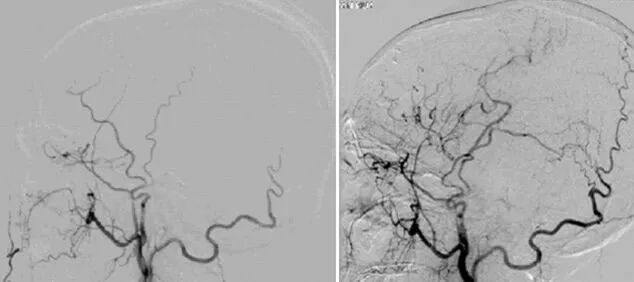

术后7天复查CTA提示血管确切吻合。

术后3个月,全脑血管造影复查见血管吻合确切,血流通畅,另外造影显示颞肌也对颅内形成了代偿供血。